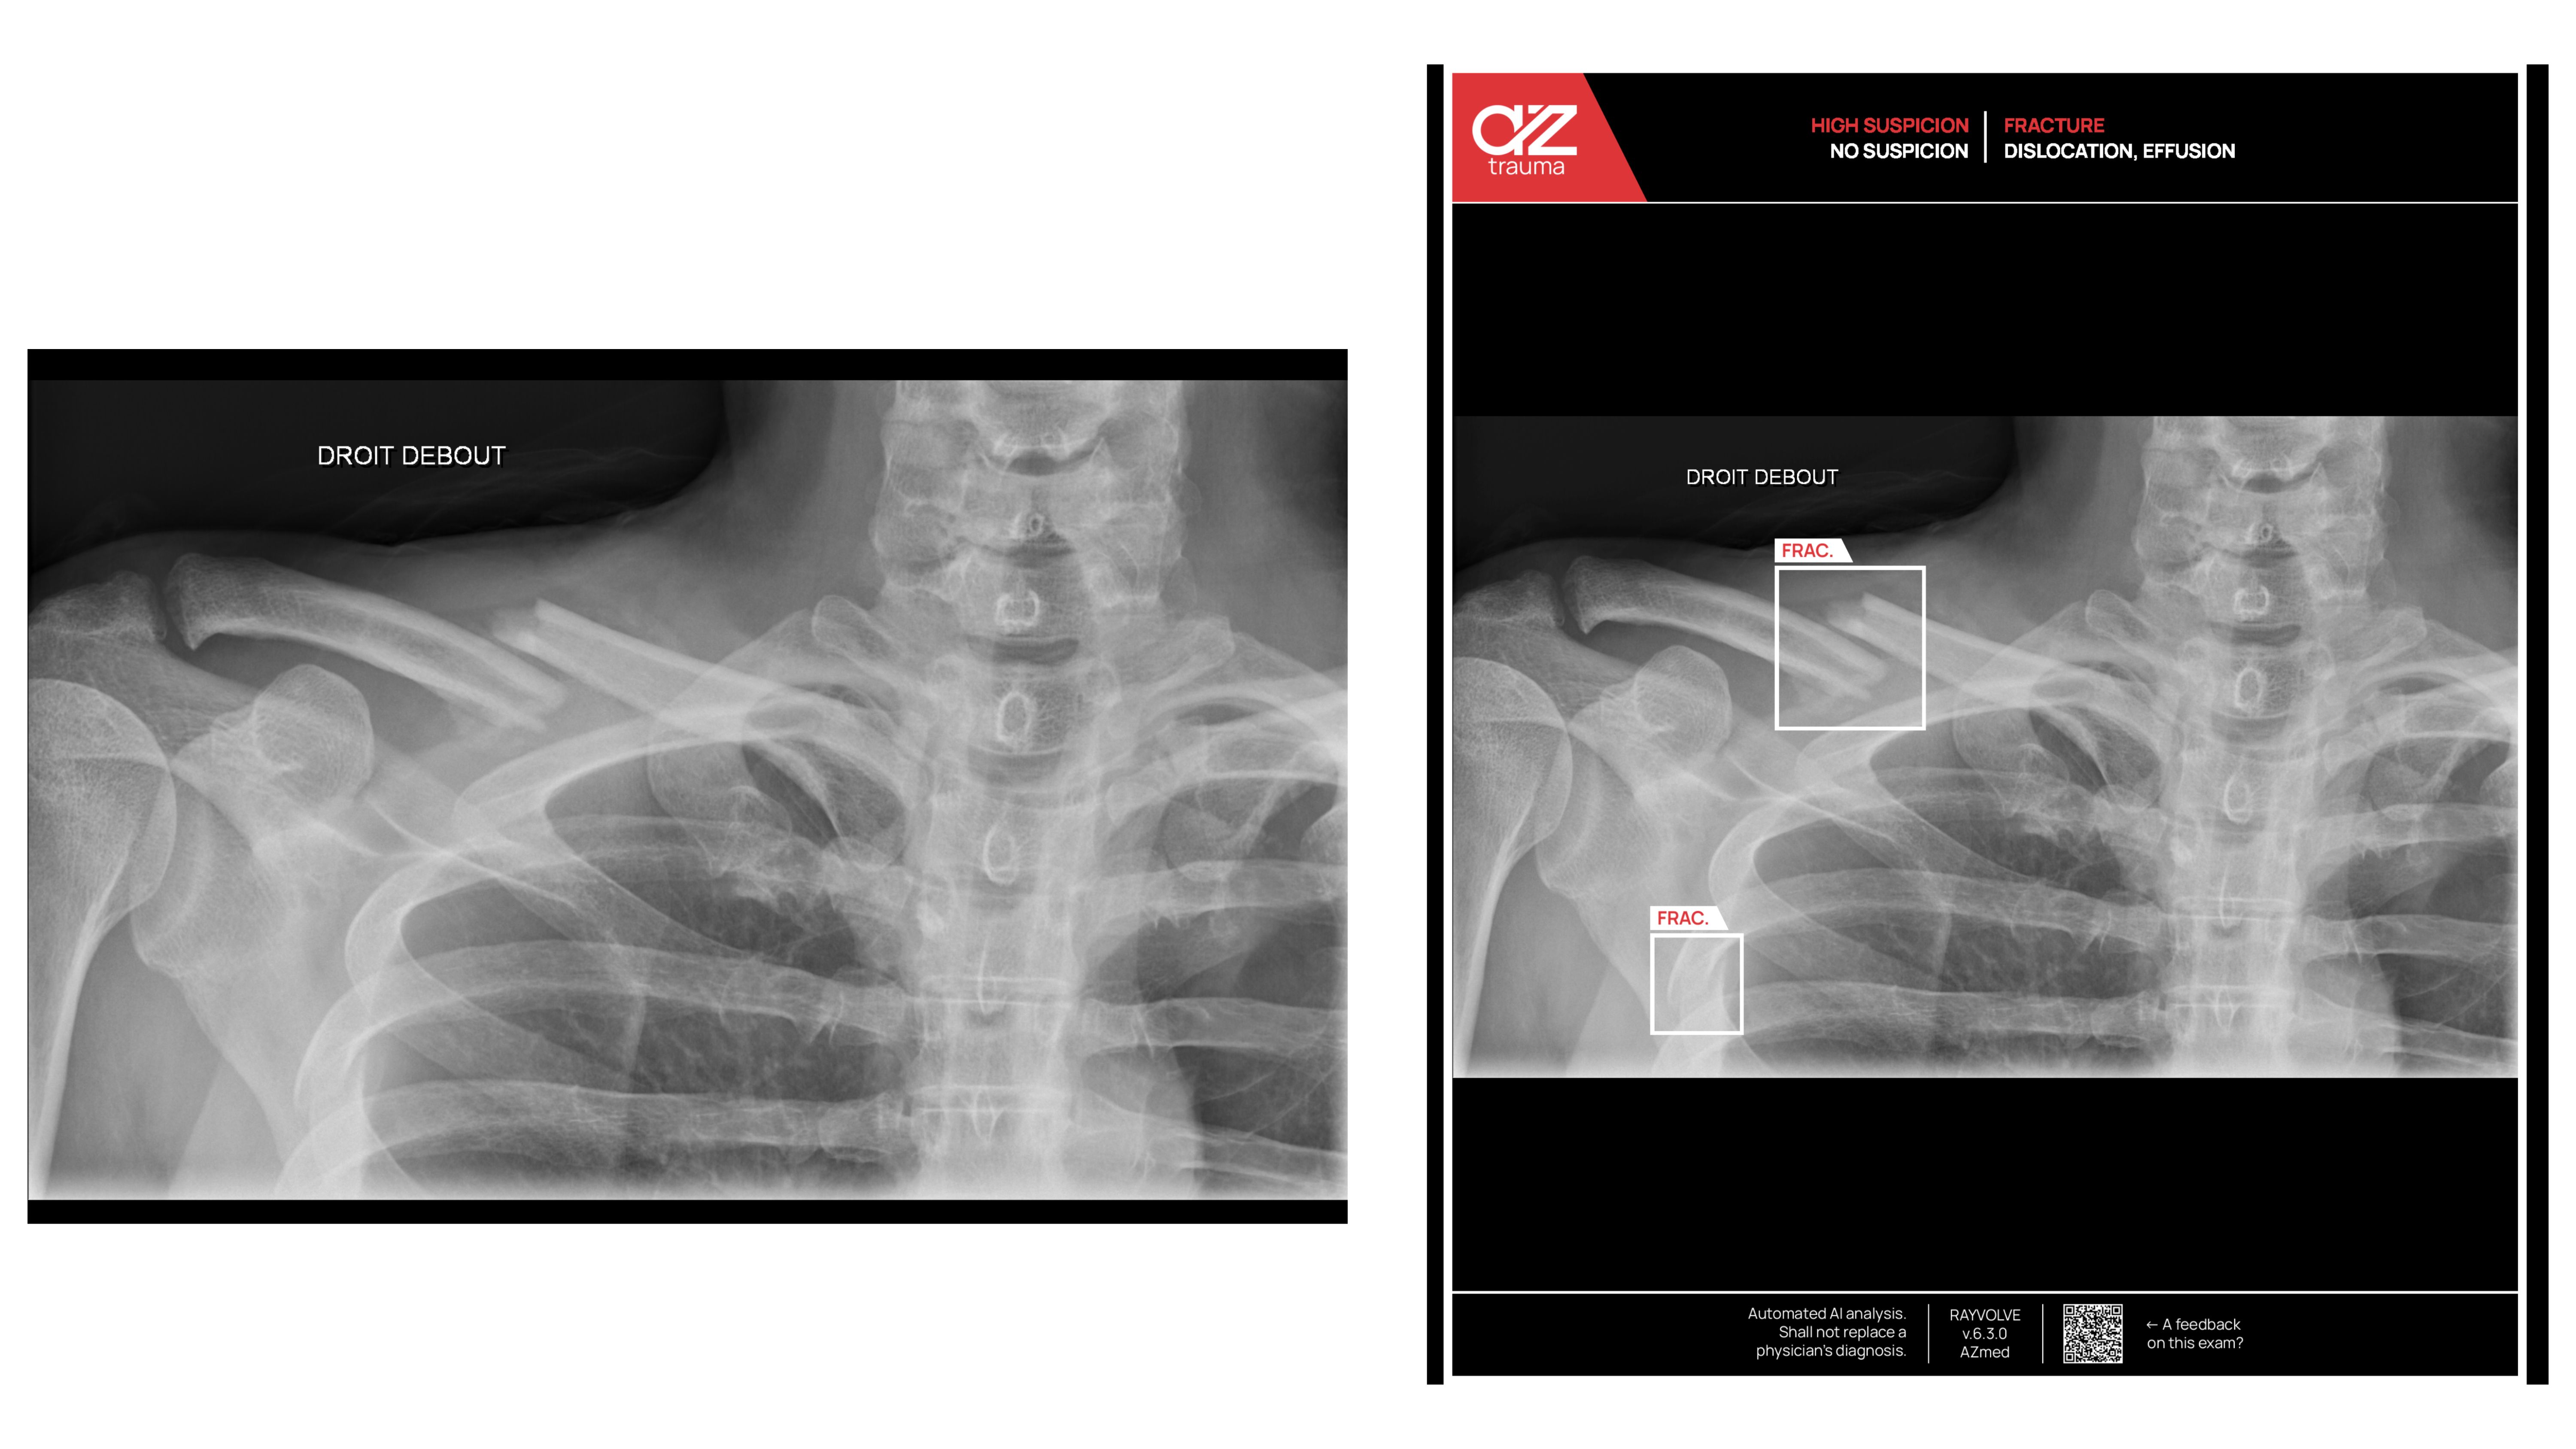

Patient Case 3: Clavicle and Rib Findings

In this instance, the Rayvolve® AZtrauma module completed an AI fracture assessment of a radiographic series, including shoulder and chest views. The system was able to identify an obvious clavicle fracture that was seen during the initial reading and also noted a rib fracture that could easily be missed due to overlapping thoracic anatomy.

The automatic localization of both lesions demonstrated that AI fracture analysis provides a “second pair of eyes” to help support diagnostic confidence, helping the radiologist be more exhaustive after detecting an obvious fracture, and mitigate the risk of missing such findings. This case illustrates the ability of AI to help radiologists to identify multiple injuries on a single study while potentially increasing accuracy and supporting reliable and consistent efficiency.